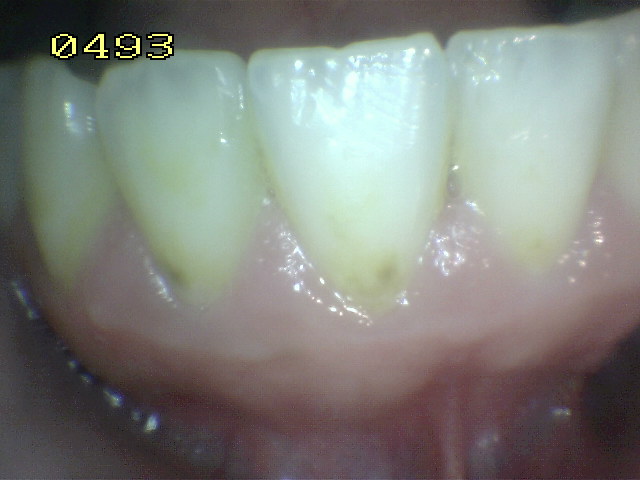

• Hacer examen visual de la superficie húmeda:

1. Inicie desde el cuadrante superior derecho del paciente

2. Prosiga con la orientación de las manecillas del reloj

3. Inicialmente el examen visual se realiza con las superficies húmedas.